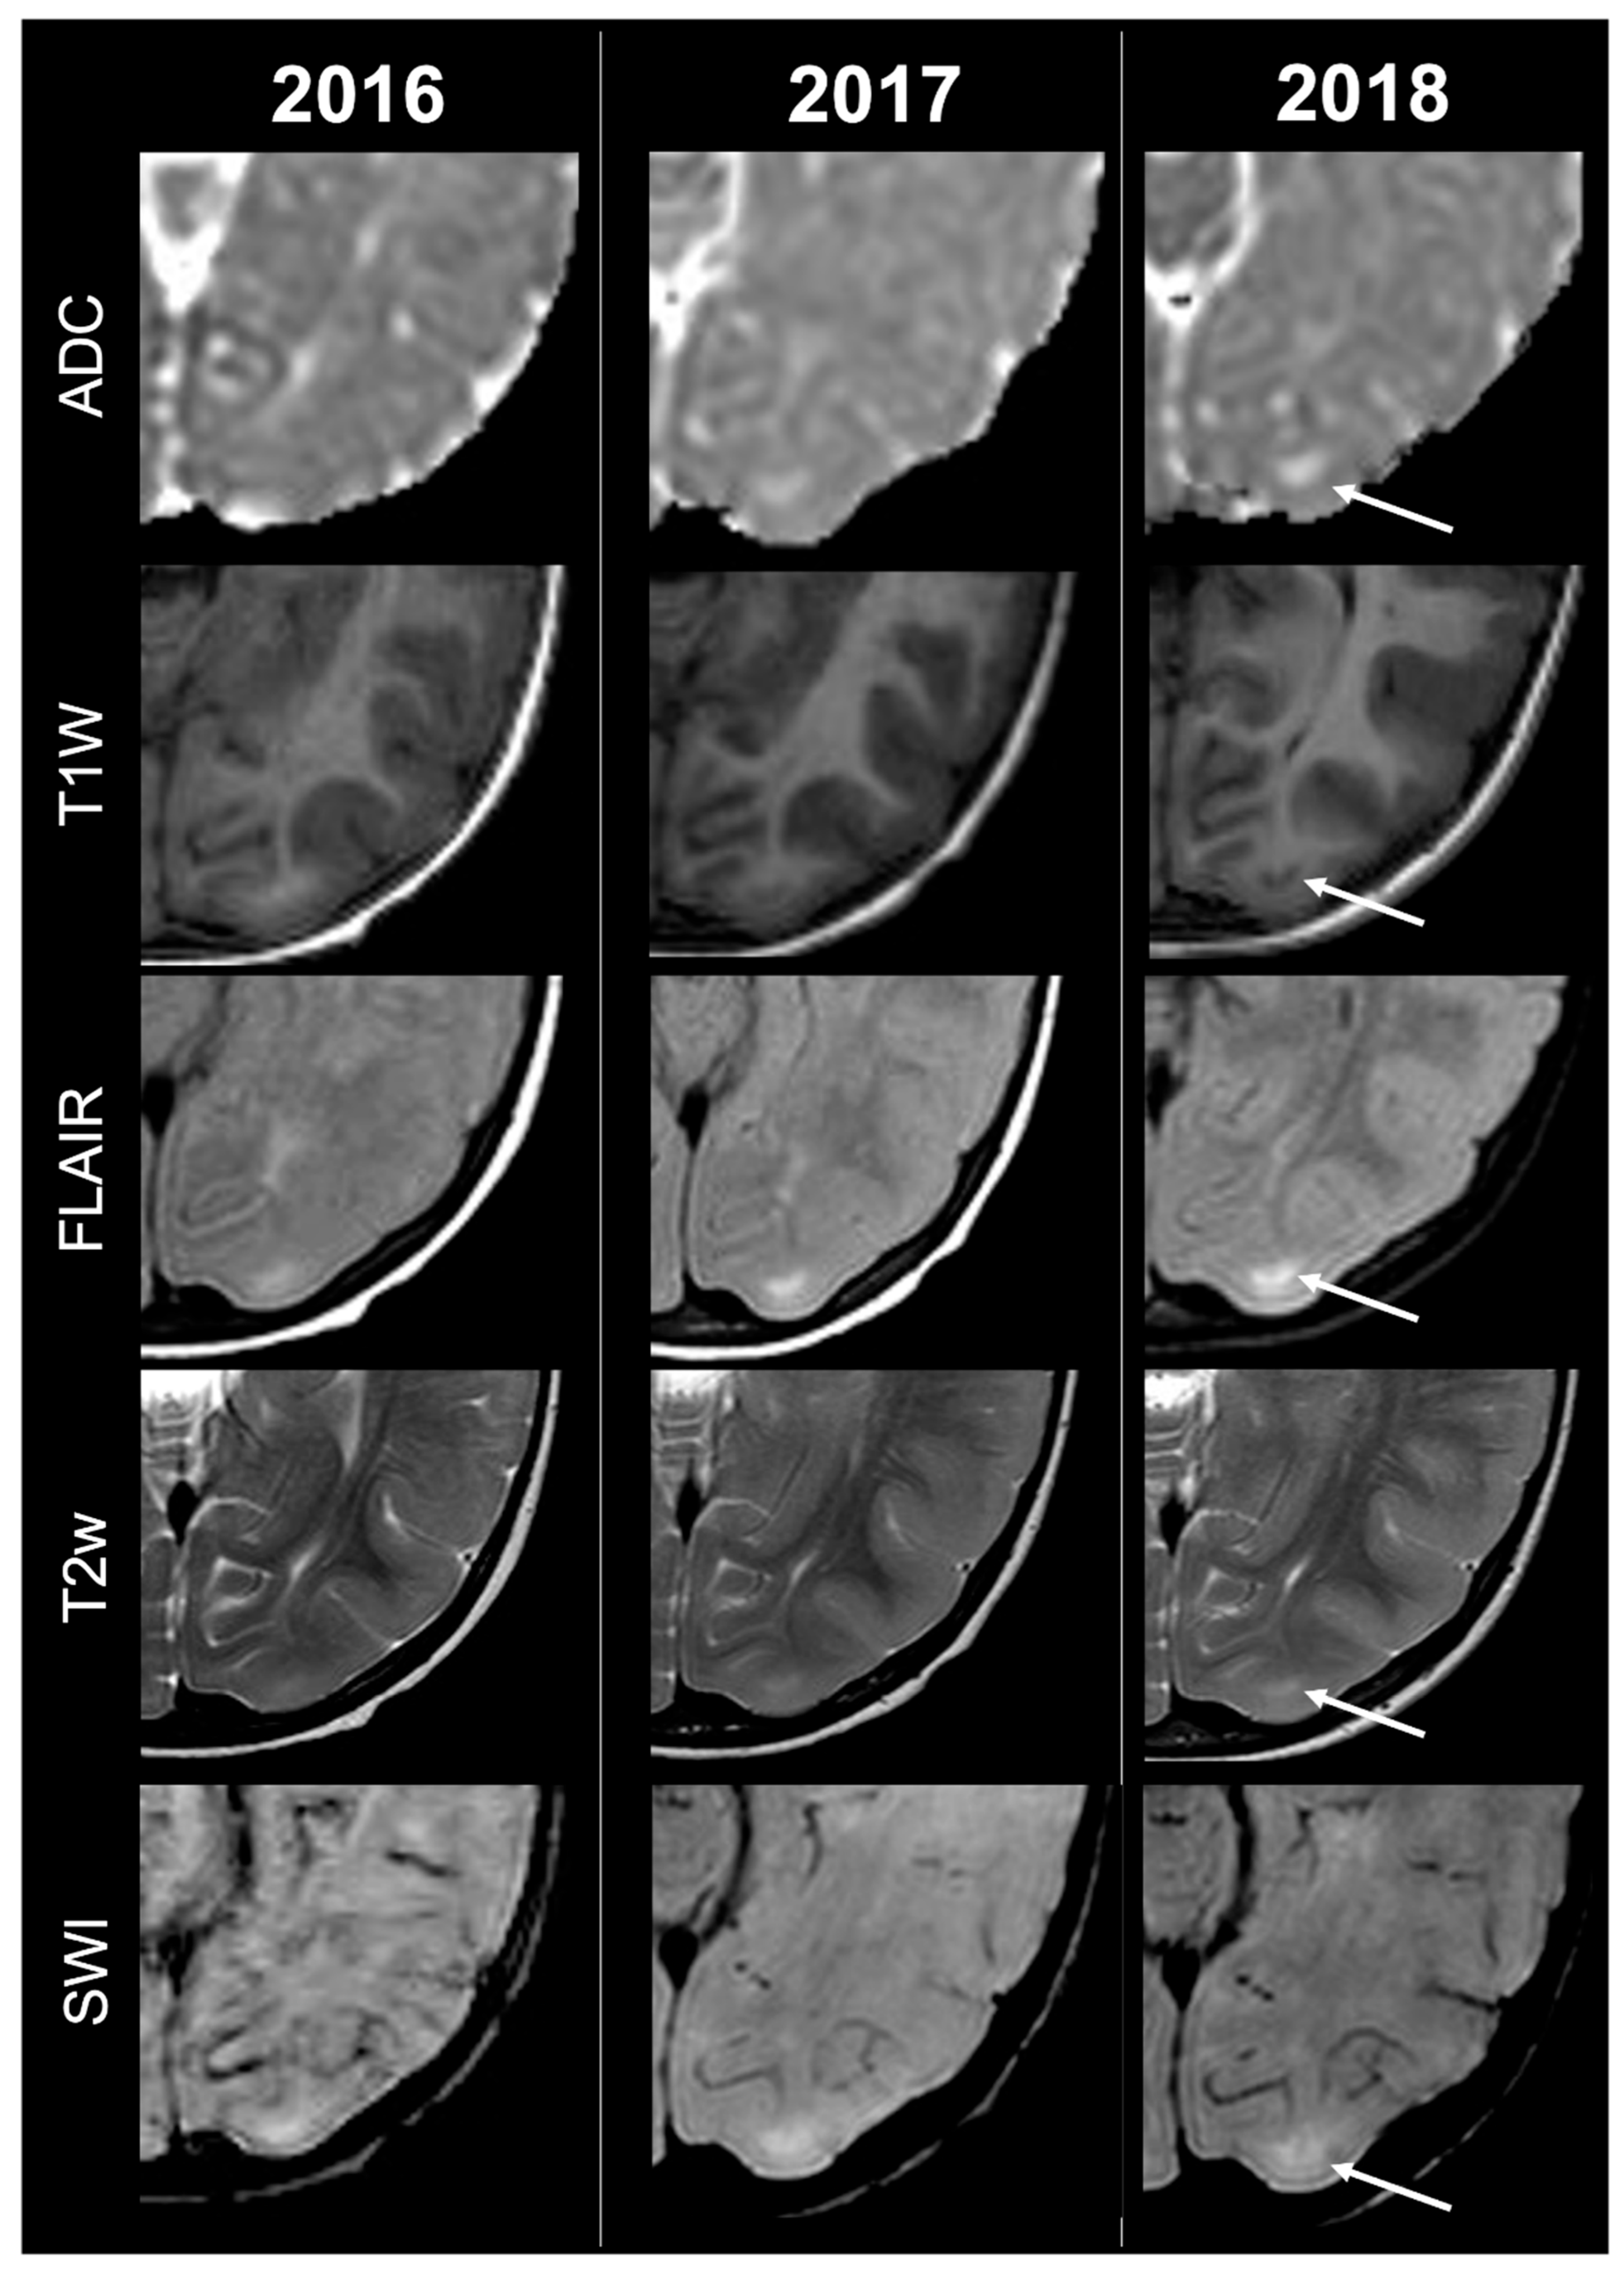

Concerning total lesion count, the interobserver agreement was excellent, with an ICC of 0.91 (95% CI: 0.87–0.95). At baseline, the total number of CTs identified across the cohort was 918 (mean ± SD = 16.1 ± 12.4), whereas at the last available MRI follow-up, the overall count increased to 1070 (mean ± SD = 18.8 ± 13.3), corresponding to a net gain of 152 CTs, equal to a relative variation of +17%. When stratified by tuber type, distinct trajectories were observed over time. Type A CTs, which were relatively abundant at diagnosis (N = 303, mean ± SD = 5.3 ± 7.0), decreased to 255 (mean ± SD = 4.5 ± 5.9) at follow-up, yielding a reduction of 48 lesions (−16%). Conversely, type B CTs showed an opposite trend, increasing from 438 (mean ± SD = 7.7 ± 8.4) at baseline to 556 (mean ± SD = 9.8 ± 8.6) at follow-up, corresponding to a net increase of 118 tubers (+27%). An example of MRI signal evolution from tuber A to tuber B is shown in Figure 1. Similarly, type C1 CTs rose from 160 (mean ± SD = 2.8 ± 4.8) to 220 (mean ± SD = 3.9 ± 5.8), with a net gain of 60 tubers (+38%). Type C2 CTs, initially rare at diagnosis (N = 14, mean ± SD = 0.2 ± 0.8), markedly expanded to 33 (mean ± SD = 0.6 ± 1.5), accounting for an increase of 19 CTs (+136%). Finally, type D CTs were only sporadically encountered, with a modest increase from 3 (mean ± SD = 0.1 ± 0.3) to 6 (mean ± SD = 0.1 ± 0.4), equating to a 100% variation. The observed increment of type C2 tubers was attributable almost exclusively to the progressive transformation of pre-existing type B lesions and, more prominently, type C1 lesions, while the increase in type C1 tubers reflected the gradual conversion of both type A and type B CTs that were already detectable at disease onset. An example of MRI signal evolution from tuber B to C1 is shown in Figure 2, while from tuber C1 to C2 in Figure 3. Only in one patient was a type C1 tuber newly identified at follow-up without clear evidence at baseline. In contrast, newly apparent tubers emerging over time but not clearly visible on baseline scans were most frequently represented by type A and type B lesions. Type D tubers were rare overall and were identified in only six lesions from four patients with a particularly high lesion burden; in all but one case they represented the evolution of type A or type B CTs (an example of MRI signal evolution from tuber A to tuber D is shown in Figure 4), while in a single case they were associated with adjacent subtle calcific foci. Overall descriptive data are summarized in Table 1.

Figure 1.

Left occipital tuber transition from type A to B at three different timepoints in a male patient diagnosed with TSC1.